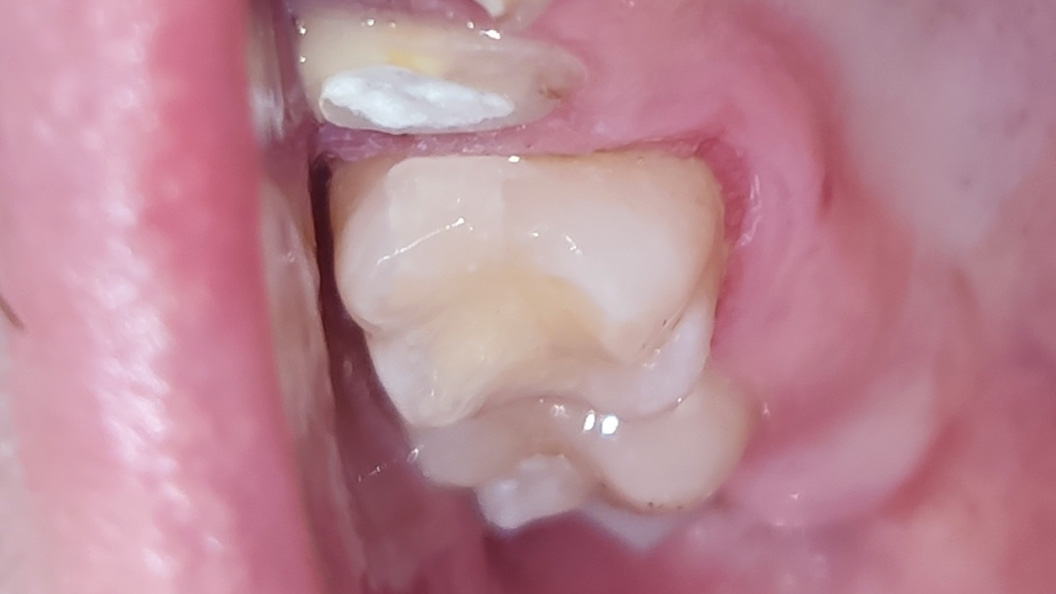

До и после лечения

Пациент обратился с жалобами на эстетический недостаток в верхнем жевательном зубе справа, который был выявлен в ходе подготовки соседних зубов под коронки. После обработки кариозной полости под контролем кариес-маркера, был выявлен кариес средней глубины, дно и стенки полости плотные. Реакция на холодовую пробу и перкуссию отрицательна. Поставлен диагноз: хронический средний кариес.